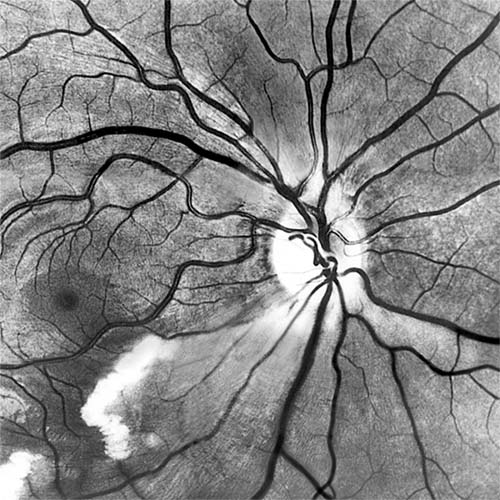

Red-free light (a white light with a green filter) allows details of hemorrhages, focal irregularity of blood vessels, and nerve fibers to be seen more clearly (Figure 15-9).

Figure 15-9: Acute retinal infarction. Red-free photograph shows acute arterial occlusion in a congenitally anomalous vessel at the disk. The inferior retina is infarcted, but axoplasm has accumulated beneath the fovea in an irregular pattern owing to preserved neuronal function of the distal ganglion cells.